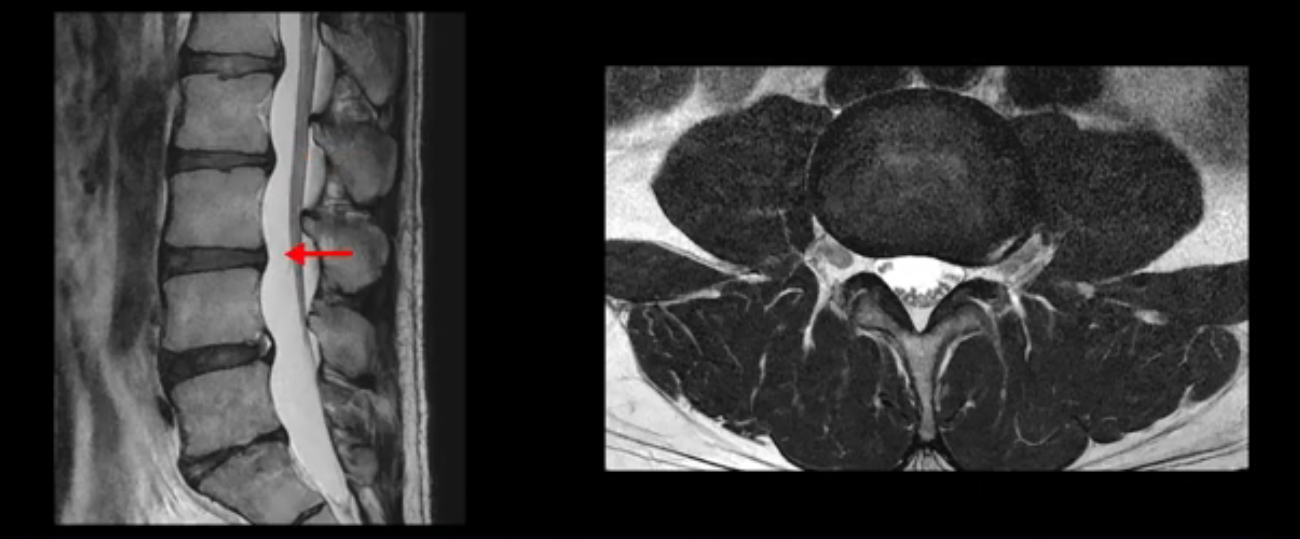

우선 이분 MRI를 보면 허리 모든 마디의 디스크가 퇴행되어 있고

여러 마디의 디스크가 조금씩 밀려나와 보이고, 디스크 섬유륜도 찢어져 보이는 마디도 보입니다.

그런데 이분의 증상과 MRI가 전혀 일치하지 않는데, 왜 그런지 지금부터 자세히 설명드립니다. 이분 증상은 앉으면 엉치와 허리가 심하게 아파 10분 이상 앉는 게 어렵고 양쪽 발가락이 앉아있을 때나 누워있을 때 다 저립니다. 걸을 때도 아파서 10분 걷기도 어렵습니다. MRI를 마디마디 살펴보면 1번 2번은 오른쪽으로 살짝 밀려나온 디스크가 있지만 전혀 심하지 않고, 뒤에 또 설명하겠지만 최근에 밀려나온 급성 디스크가 아니고 오래된 디스크로 판단됩니다.

2번 3번도 비교적 디스크 상태는 좋고 신경 구멍 넓이도 아주 넓습니다.

3번 4번도 마찬가지로 디스크상태 좋아 보이고 신경 눌림 전혀 없어 보입니다.